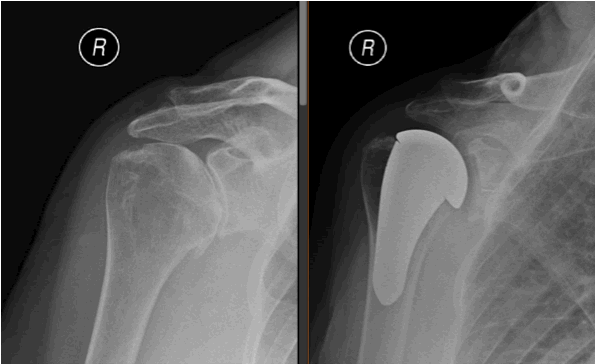

Stemmed shoulder replacement: This is the conventional type of shoulder replacement. The ball of the joint is cut and a metal prosthesis with a stem is implanted in the humerus. If only the ball of the joint is replaced the procedure is called a Hemiarthroplasty. If the glenoid is replaced at the same time the procedure is referred to as a Total shoulder replacement.

In a reverse shoulder replacement the orientation of the joint is changed such that an artificial ball is fixed to the shoulder blade and a socket is fixed to the humerus. A reverse shoulder replacement is used in patients where the rotator cuff is torn or deficient.